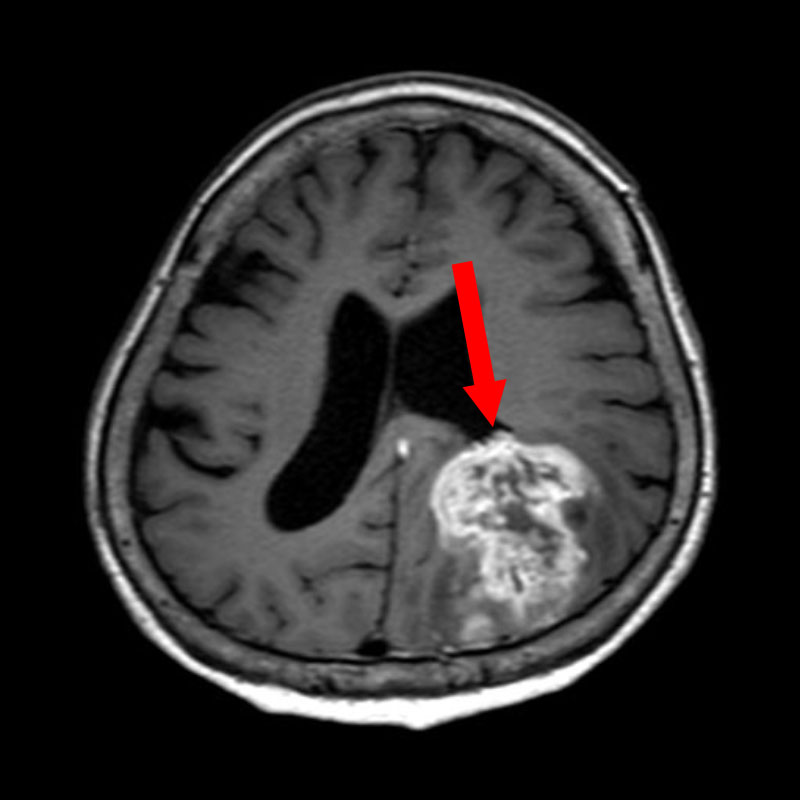

624

'25年4月

70代

後頭葉膠芽腫

頭蓋内腫瘍摘出術

No.’25_26 手術前1

No.’25_26 手術前2

No.’25_26 摘出 前

No.’25_26  摘出 中

No.’25_26 摘出 後